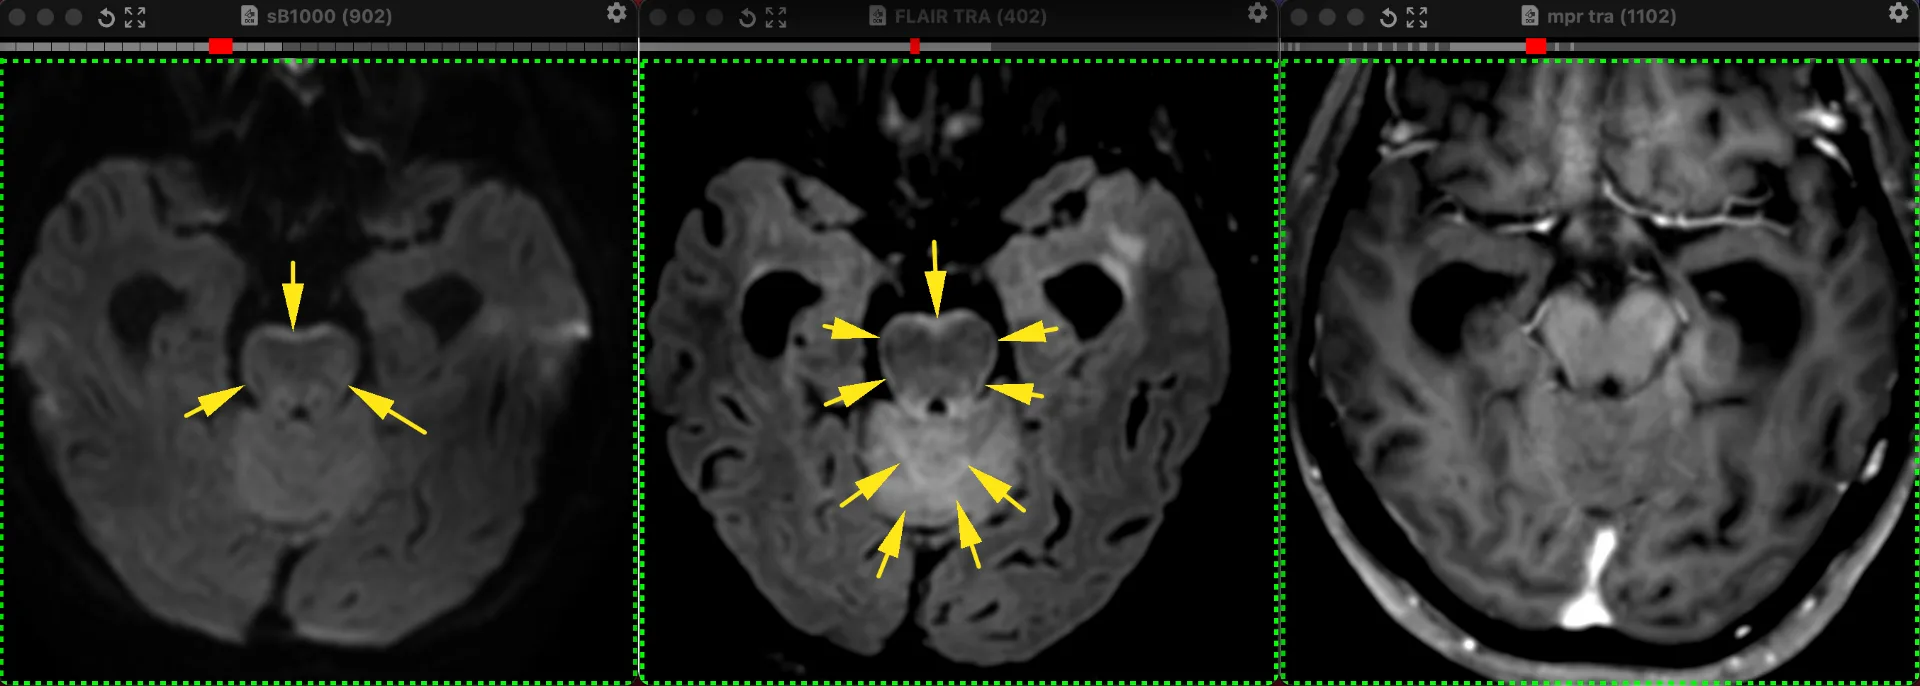

А Вы вообще, в курсе, что лептоменингиальные метастазы, как внечерепных, так и внутричерепных опухолей, могут не накапливать контраст? У пациентки 74 лет 01.03.2026 года - ухудшилось состояние, начала подволакивать правую ногу, перестала отвечать на вопросы, пациентка в сопоре с 02.03. Имеется как бы обведённый фломастером на FLAIR и DWI ствол, ну и гиперсигнал на FLAIR в субарахноидальных пространствах мозжечка с отёком самого мозжечка. И арезорбтивная гидроцефалия с декомпенсацией. А накопления контраста нет.